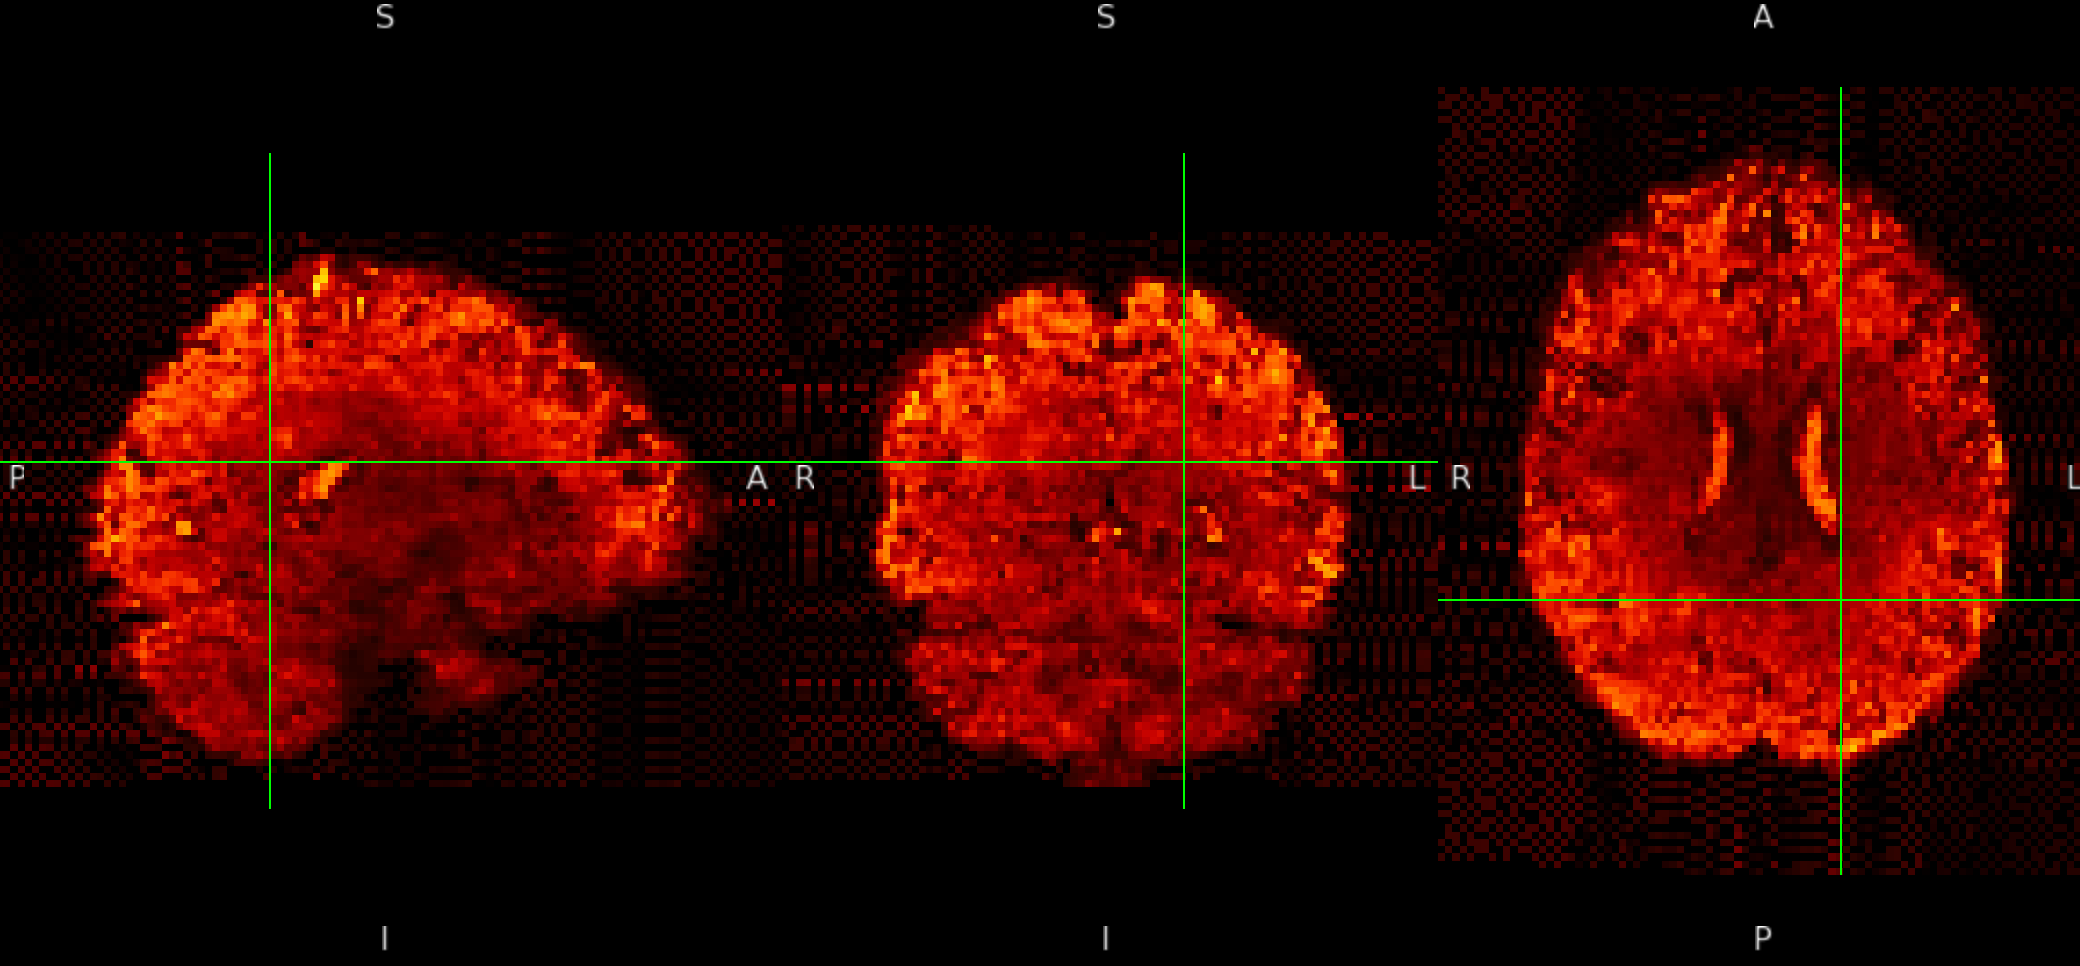

ME sequence in MNI152NLin6Asym-res1

The checkerboard pattern is more evident in the ME sequence where it is also visible outside the brain, but it is present in both, ME and SE inside the brain.

- why is this pattern visible only at MNI 1mm resolutions? Please remember that my voxels are between 1.2 and 1.5 mm isotropic.

- Could this be related to the Lanczos interpolation?

- why is the pattern exacerbated in the ME sequence? Is it the echo combination?